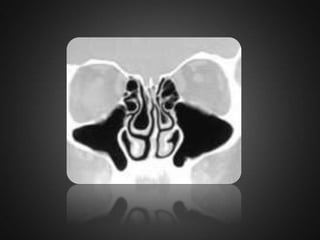

VARIATIONS IN MIDDLE TURBINATE Concha bullosa is a variation originated from pneumatization of the bone plate by extension of ethmoid sinus cells.  Such variation may be either uni- or bilateral.  Varied degrees of pneumatization of the concha may be observed, possibly causing middle meatus or infundibulum obstruction.